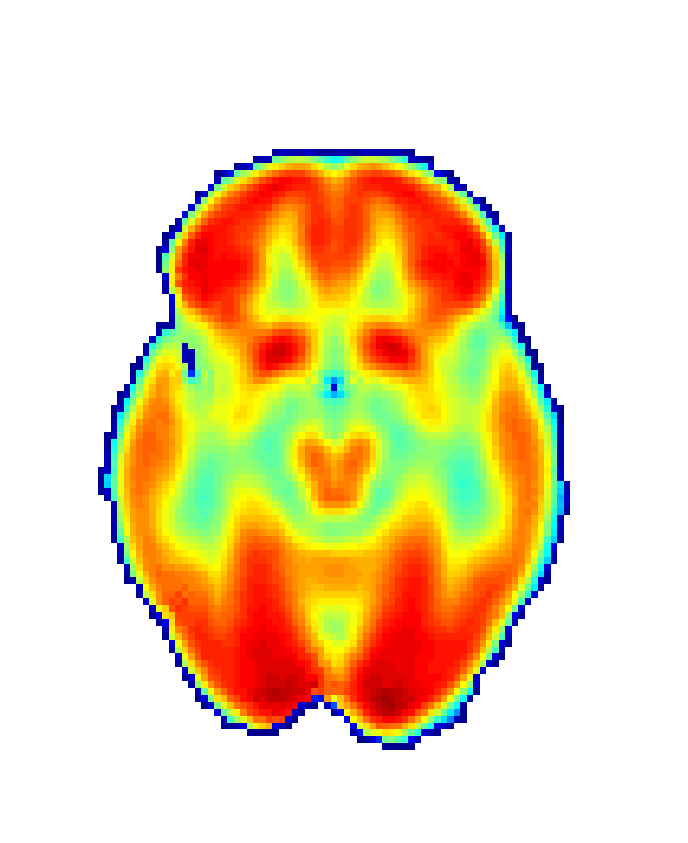

In order to obtain 18F-FDG PET data we drawn upon the Alzheimer’s Disease Neuroimaging Initiative (ADNI) [56], a platform that collects data from different research institutions focusing on AD diagnosis. We selected 18F-FDG PET and MRI data, together with demographic information (age and sex) for CN group (75 patients; 44 male; age: 75.56±4.96plus-or-minus75.564.9675.56\pm 4.96 years) and AD group (51 patients; 30 male; age: 74.03±7.25plus-or-minus74.037.2574.03\pm 7.25 years) summing 126 participants. Images were then realigned, unwrapped, co-registered with MRI data, spatially normalised, mean proportionally scaled, and masked following standard procedures deployed by SPM with the aim of guaranteeing voxel-to-voxel comparability between images (see Figure 2).

Refer to caption

(a) Raw image

(b) Normalized image

(c) Masked image

Figure 2: Stages of 18F-FDG PET processing. (a) Raw image obtained from ADNI, (b) image after anatomical standardization, (c) processed image after masking.